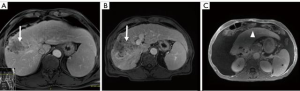

Surgical resection remains the gold standard local treatment of primary and metastatic liver malignancy. Many patients are not candidates for resection at presentation due to disease stage, performance status, comorbidities, anatomic factors, or insufficient FLR. PVE and ALPPS have been utilized in patients with inadequate FLR but are associated with a risk of tumor progression and significant morbidity/mortality, respectively (15,16,44-48) (Figure 1). Furthermore, post-operative liver failure remains the most common morbidity after both PVE and ALPPS (19,20).

Liver volumetrics and growth kinetics have been used as surrogates of post-operative liver function, but the variability of a patient’s hepatic substrate is not completely captured by these indirect measures of physiology. Liver volumetrics may be prone to additional error in patients with underlying liver disease and previous systemic therapy. It is known that PVE and ALLPS reduce FRS hepatic function however, pre-operative devitalization of the FRS is not achieved with either of these techniques and liver failure remains a major associated morbidity and mortality. TARE induced devitalization of the FRS may represent a more accurate surrogate for post resection liver function as the patient is not physiologically relying on the FRS at the time of surgery (Figures 2,3). This is supported by the low incidence of PHLF in our cohort (3.8%). Conceptually, growth metrics such as DH and KGR may be less informative of the risk of PHLF in the setting of a devitalized FRS as the liver may not hypertrophy beyond what is adequate for the individual patient.